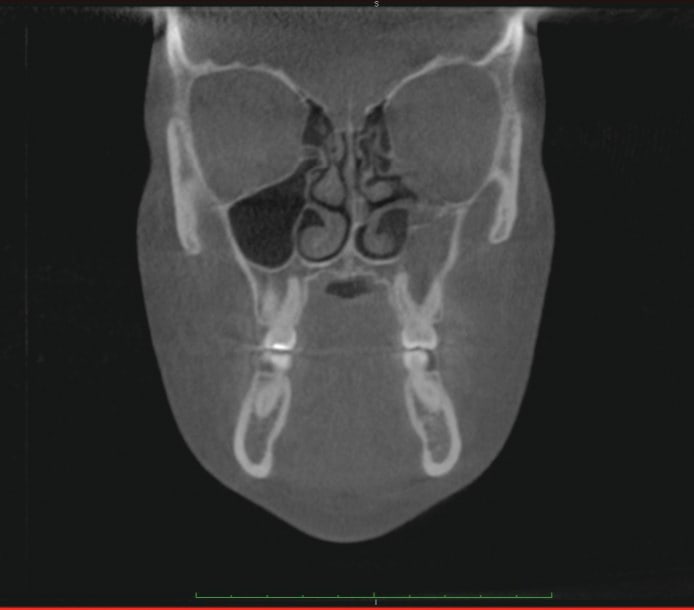

1. Many have advocated that the use of 3D imaging is certainly useful in treating patients with impacted maxillary canines. This is certainly true. However, only 1 to 2 percent of the population has impacted canines. The population of most orthodontic practices is published that 5 percent of the practice’s patients seeking treatment have impacted canines. If this is the main reason for taking DICOM images on patients, then these images should be outsourced. The cost of purchasing a 3D machine for 5 percent of the office’s patients does not make financial sense. A 2-dimensional pan or ceph does not adequately image the impacted teeth for not only surgical planning but also the mechanics needed to move these teeth into alignment. It has been reported that 62% of palatally impacted canines are touching the roots of laterals and centrals. This is information that 3D imaging illustrates. This could often change the mechanics needed to properly position the canines without damaging the roots of adjacent teeth. However, the 3D imaging of impacted teeth certainly is advantageous to the orthodontist or oral surgeon that will surgically expose the non-erupted teeth. This is illustrated in Figure 1 through Figure 3. One can readily see the benefits to the patient for using 3D imaging technology for the treatment of impacted teeth.